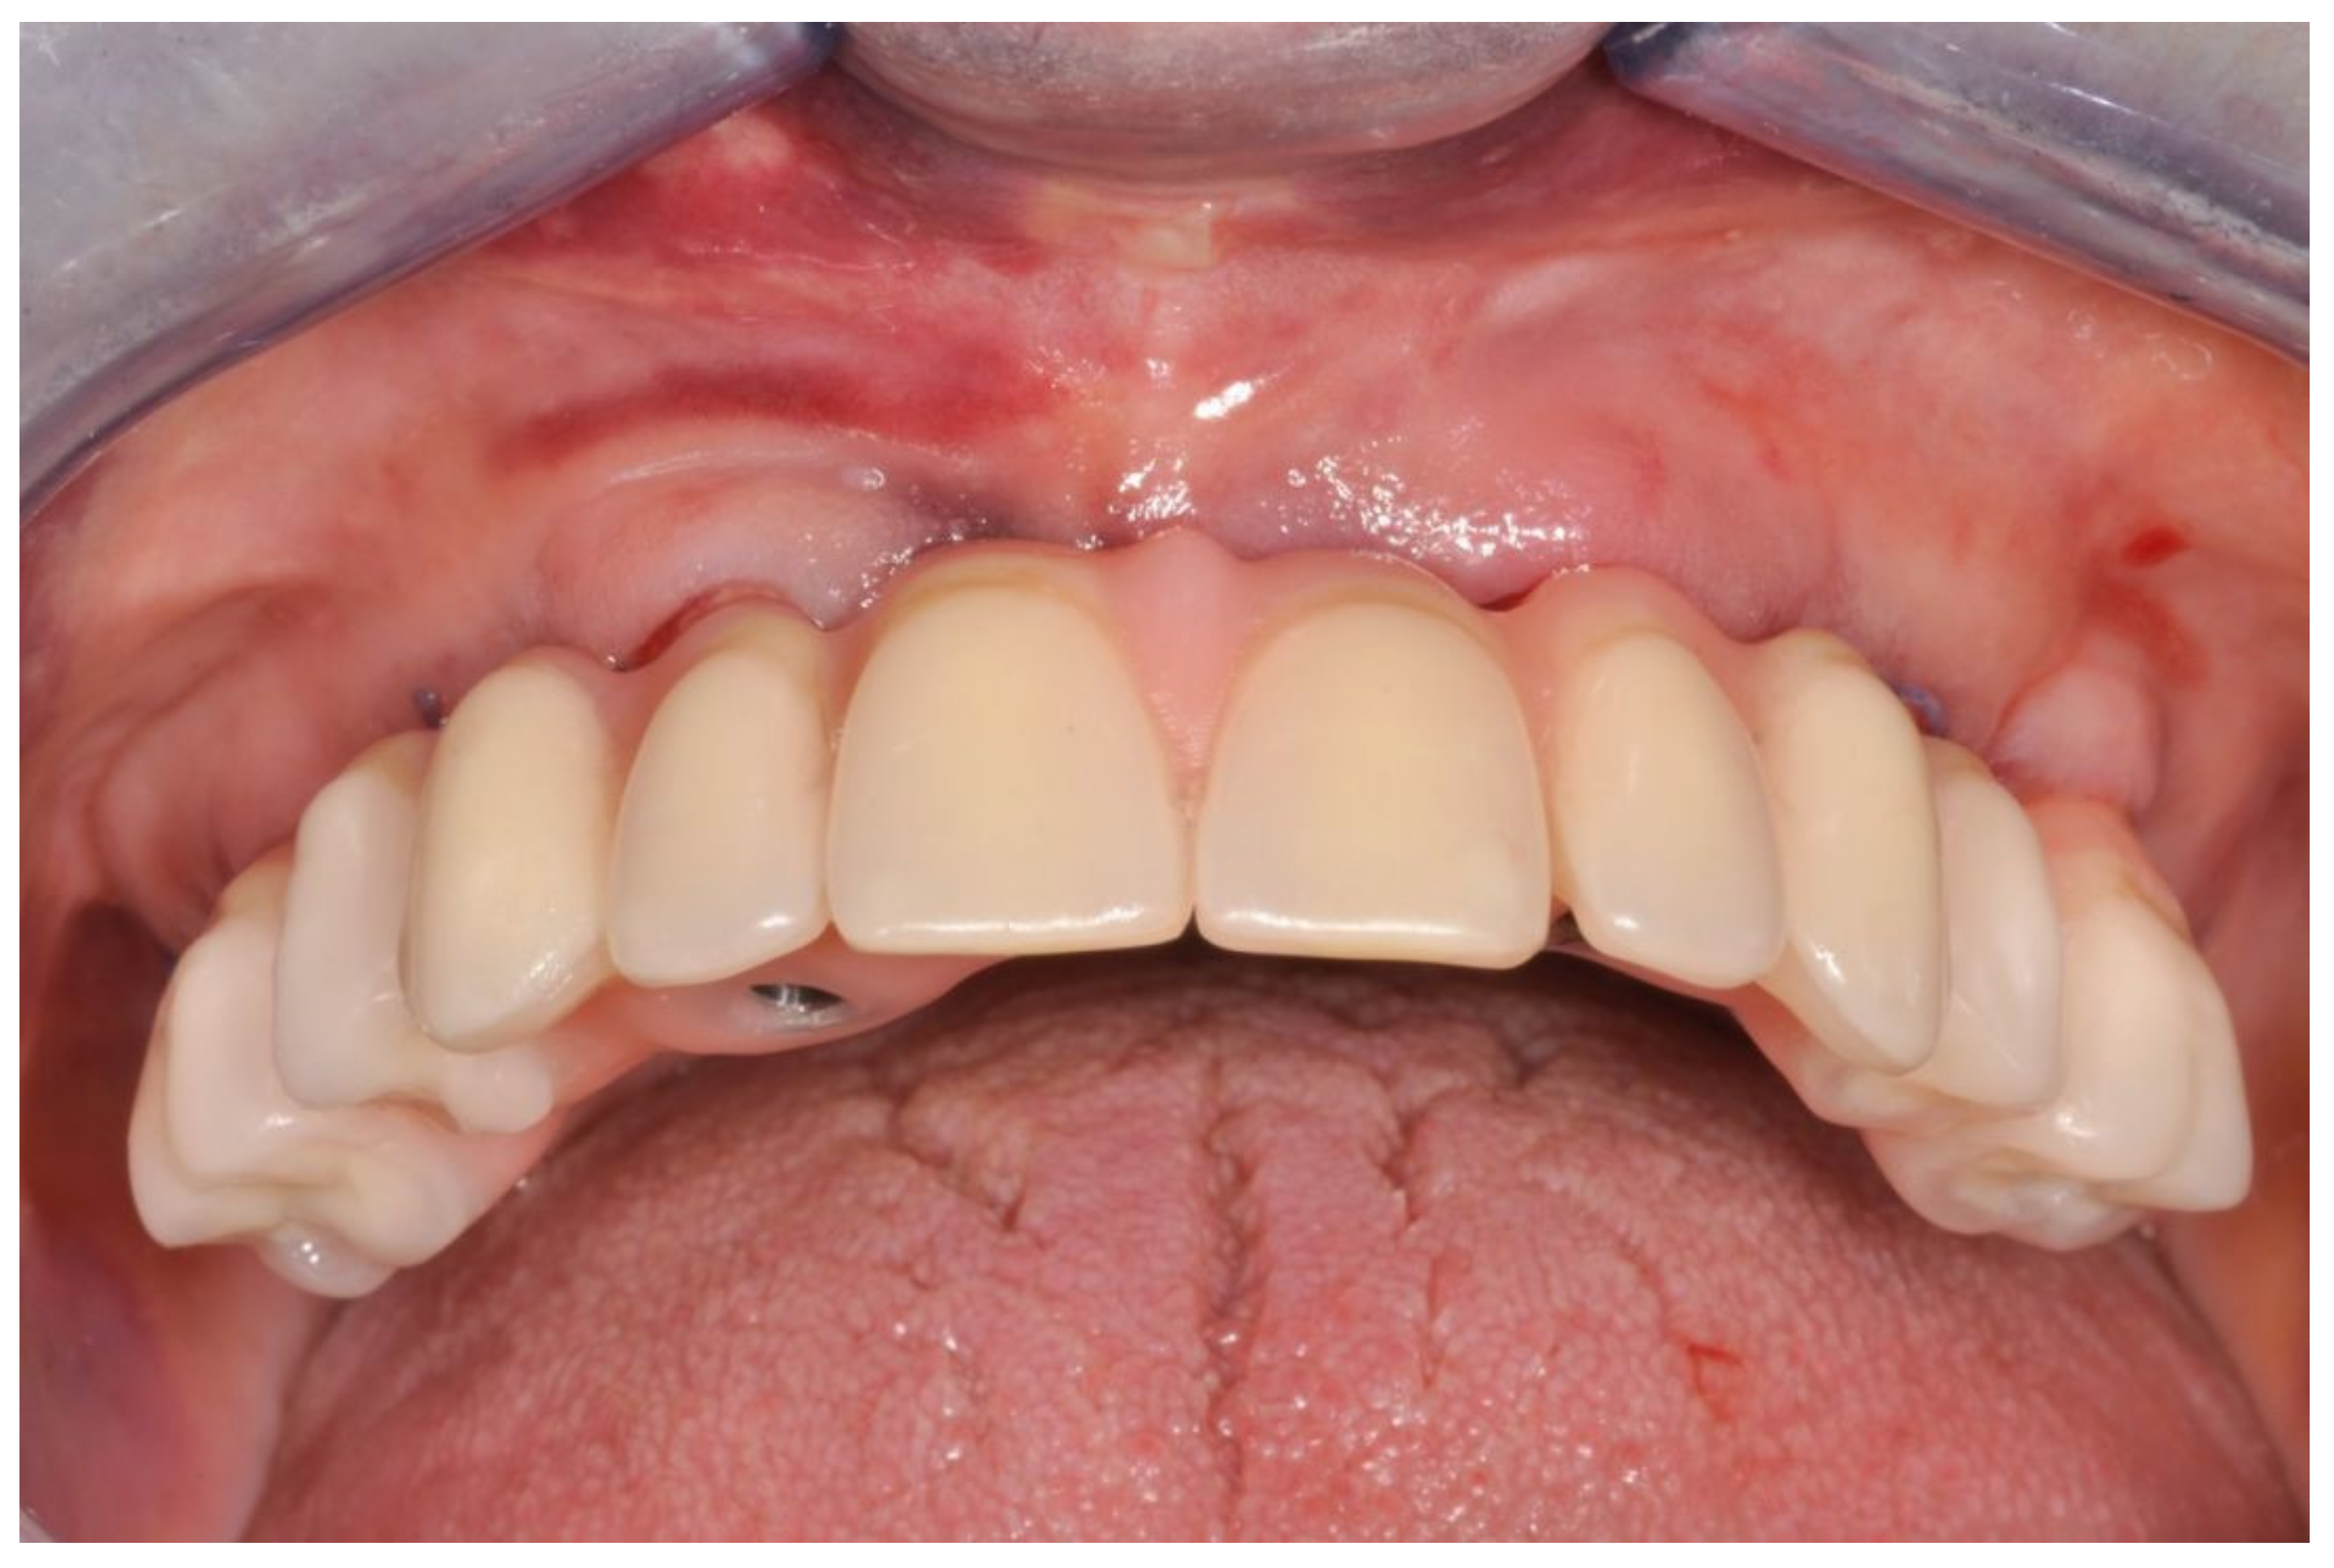

Figure 4.

Interim prosthesis without cantilevers.

Figure 5.

Interim prosthesis after implant placement.